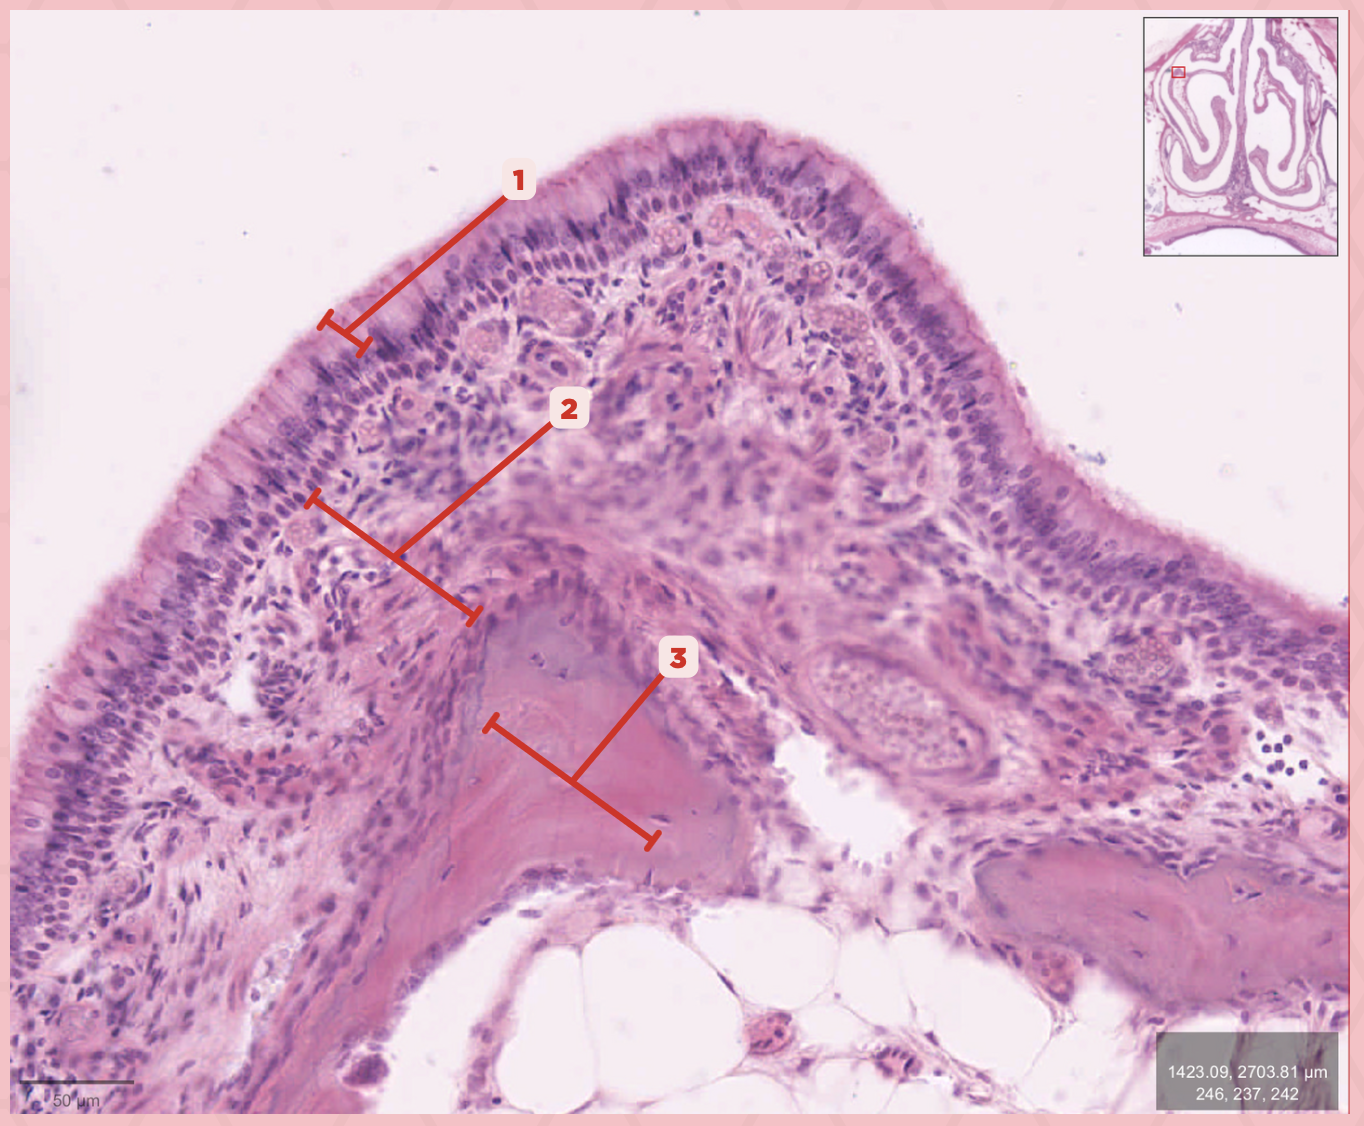

Respiratory Epithelium

Identify the structure labeled as 1.

Lamina Propria

Identify the structure labeled as 2.

Bony spicule

Identify the structure labeled as 3.

Respiratory Epithelium

What epithelium lines this structure?

Ciliated pseudostratified epithelium

What type of epithelium lines this structure?

Respiratory Epithelium

Identify the structure labeled as 1.

Mucosa

Identify the structure labeled as 2.

Bone

Identify the structure labeled as 3.

Keratinized stratified squamous epithelium

What’s the lining epithelium at #3?

No

Are Glands present at #1?

Lamina Propria

Identify the structure labeled as 1.

Adipocytes

Identify the structure labeled as 2.

Keratinized stratified squamous epithelium

Identify the structure labeled as 3.